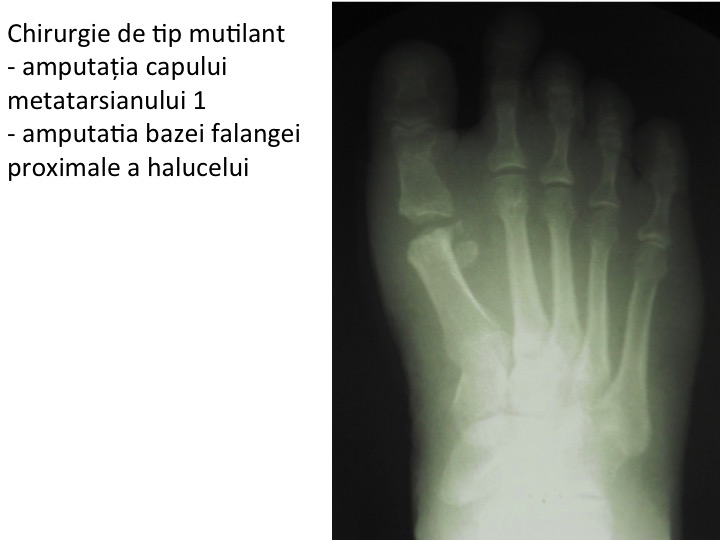

- consecinta procedurilor chirurgicale mutilante articular (Schede, Keller, Mayo etc);

- in aceste tehnici se indeparteaza componente ale articulatiei degetului mare (metatarso-haluciana), in speranta unei reintegrari sociale rapide, utilizand procedee chirurgicale foarte simple;

- corectia secundara este extrem de dificila, ca urmare a lipsei de substanta osoasa de la nivelul capului primului metatarsian ;

- este urmarea unor proceduri mutilante de tip Schede, Keller, Mayo, ce amputeaza segmente ale articulatiei "degetului mare" (metatarso-haluciana).

- tehnica de amputatie tip Schede inlatura o portiune de os sanatos ("exostoza"), mutiland inutil capul metatarsianului;

- tehnica de amputatie Keller elimina baza falangei proximale a halucelui ;

- metatarsianul 1 ramane proeminent, in schimb halucele devine balant, datorita decuplarii sale de sistemul muscular flexor scurt;

- urmarea unor procedee chirurgicale mutilante, de tip Keller, Mayo etc;

- amputatia unor componente ale articulatiei provoaca destabilizarea acesteia, cu importante consecinte biomecanice;

- amputatia bazei falangei proximale (procedeu Keller) determina retractia sesamoidelor si metatarsalgie M1, precum si scurtarea halucelui, care devine balant (lipsit de control si de stabilitate);

- amputatia bazei falangei proximale a halucelui (procedeu Keller), prin suprimarea actiunii muschiului scurt flexor al halucelui, provoaca hiper-extensia compensatorie a falangei distale ("cook-up deformity");

corectia acestui gen de chirurgie mutilanta este deosebit de dificila, necesitand re-armonizarea lungimii si pantei metatarsienelor restante, dupa principiile chirurgiei globale a ante-piciorului.. - amputatia capului primului metatarsian (procedeu Mayo) destabilizeaza intregul ante-picior, atat estetic dar mai ales functional ;

- se produce retractia degetului mare (haluce), prin scurtarea masiva a "primei raze" ;

- halucele ramane balant si apare deformatia « cook-up » ;

- faza finala de propulsie a corpului (ultima faza a pasului) este anulata, mersul devenind unul schiopatat ;

- sprijinul pe primul metatarsian se anuleaza, transferandu-se pe metatarsienele laterale, cu aparitia metatarsalgiei de transfer ;

- finalmente apare tabloul de picior destructurat.